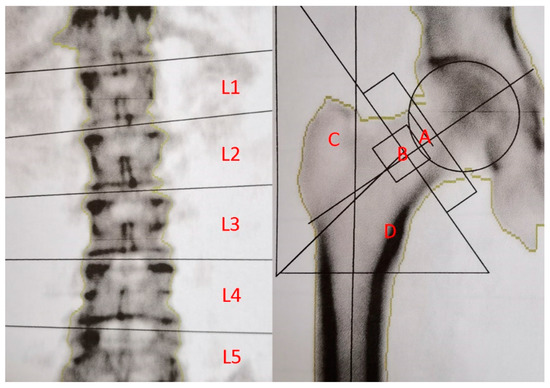

| T value (Total femoral) | −0.779 ± 1.645 | −0.289 ± 1.076 | −1.026 ± 1.823 | 0.001 |

| T value (Femoral neck) | −0.158 ± 2.238 | 0.263 ± 1.651 | −0.365 ± 2.463 | 0.084 |

| T value (Wards triangle) | −1.221 ± 1.855 | −0.774 ± 1.432 | −1.447 ± 2.004 | 0.023 |

| T value (Greater trochanter) | −1.043 ± 1.341 | −0.564 ± 1.115 | −1.285 ± 1.383 | 0.001 |

| T value (Total lumbar) | −0.429 ± 1.446 | −0.124 ± 1.465 | −0.567 ± 1.412 | 0.046 |

| T value (Lumbar nadir) | −0.943 ± 1.382 | −0.554 ± 1.415 | −1.139 ± 1.329 | 0.008 |